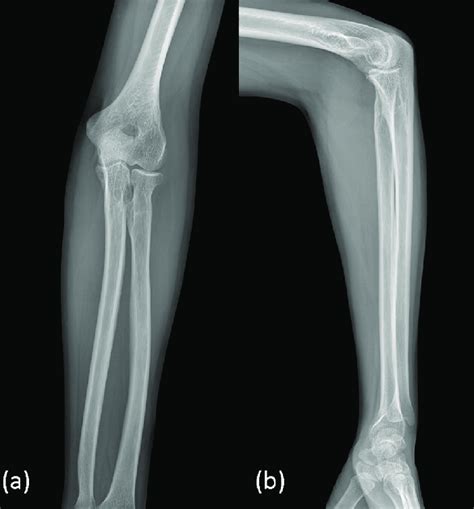

The ap view ( fig. Web a recommended systematic checklist for reviewing musculoskeletal exams is: The ap view ( fig. An elevated posterior fat pad is never normal, and a fracture or ligamentous injury.

Left Elbow X Ray Image - An elevated posterior fat pad is never normal, and a fracture or ligamentous injury. The ap view ( fig. Web a recommended systematic checklist for reviewing musculoskeletal exams is: Oblique radiograph of the elbow with labels. Web anatomy, elbow, msk.